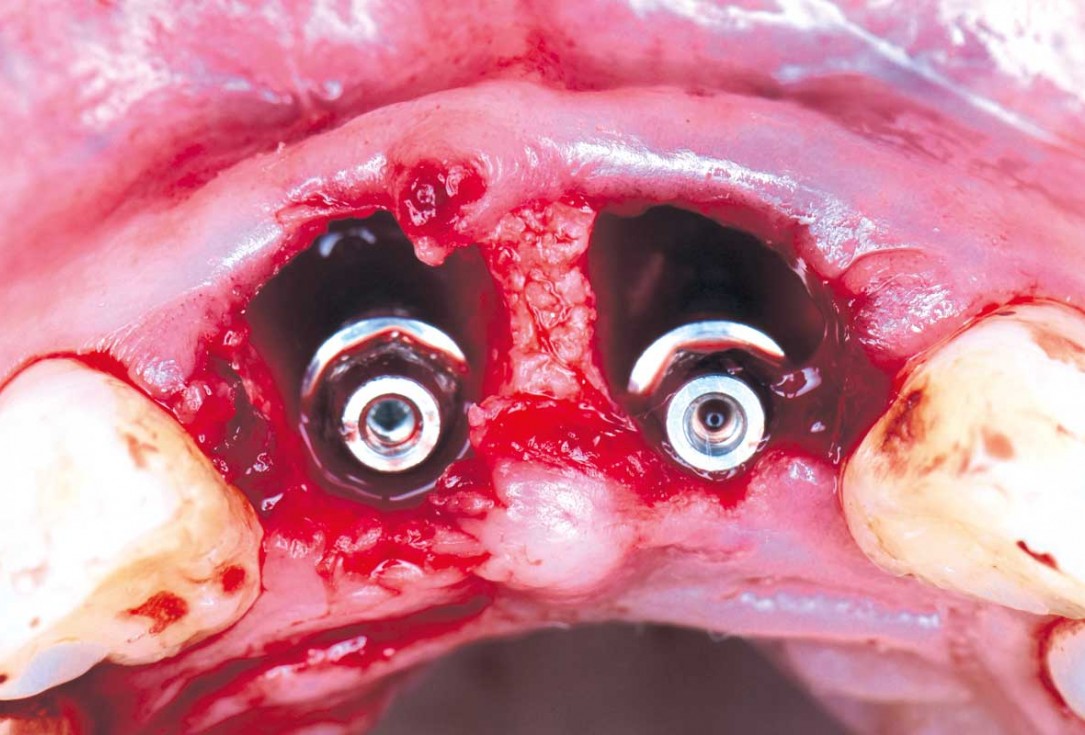

05/22 - Immediate implants are placed after extraction and the gap is filled with cerabone®cerabone® and mucoderm® for immediate implantation in the aesthetic area - Dr. D. Robles